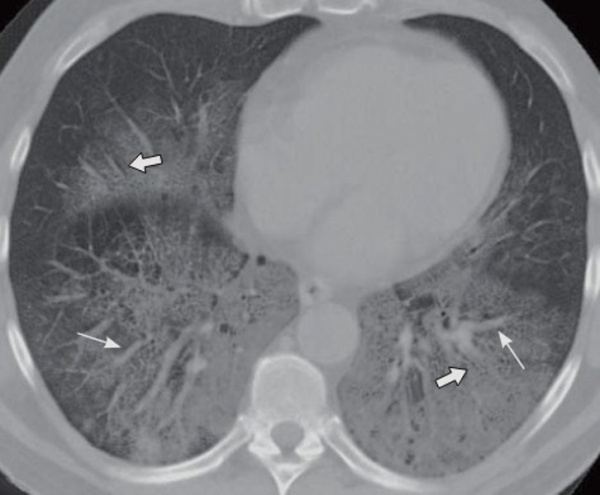

• КТ грудной клетки. При рентгенологическом исследовании выявляют двустороннее сегментарное или долевое уменьшение пневматизации легочной ткани (симптом матового стекла), утолщение междольковых перегородок (симптом булыжника). В более поздних стадиях видны участки фиброза, утолщение междолевой плевры.

Компьютерная томография грудной клетки. Феномен матового стекла.